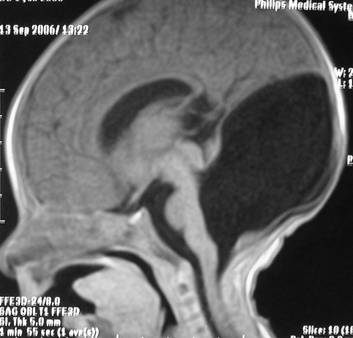

DWM arka çukur denen kafatası içinde beyincik, beyin sapı ve dördüncü karıncığın yer aldığı boşluğun doğumsal kusurudur. Beyinciğin vermis denen orta kısmı ya hiç gelişmemiştir ya da çok az bir kısmı gelişmiştir. Dördüncü karıncık genişleyip kistik bir hal almıştır (Resim 1). Bu kistik genişleme beyin omurilik sıvısının (BOS) dördüncü karıncığı terk ettiği deliklerin kapalı olmasına bağlanmaktadır. Bu hastaların %90’ında hidrosefali bulunmaktadır ve %75-80’inde doğumdan sonra ilk 3 ayda hidrosefali mevcuttur. DWM 25000-30000 canlı doğumda 1 görülmektedir.

a b c

Resim 1: (a ve b)Yatay MR görüntülerinde beyinciğin orta kısmının (vermis) gelişmemiş olduğu ve dördüncü karıncığın genişlemiş olduğu, (c) yan MR görüntüsünde kistik dördüncü karıncık izlenmektedir.